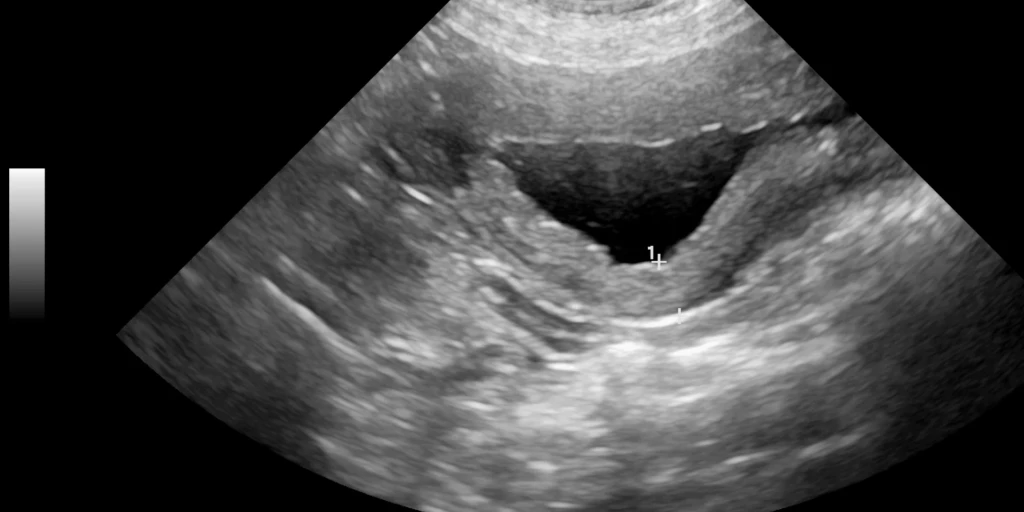

Blasentumore verursachen keine Blasenentzündung, zeigen aber ähnliche Symptome wie Harnsteine oder Blasenentzündungen. Eine genaue Diagnose erfordert eine Ultraschalluntersuchung, da Tumore so gut sichtbar sind.

Blasentumore sind meist bösartig und treten vor allem bei Katzen über zehn Jahren auf. Da sie lange schmerzfrei bleiben, werden sie oft erst im fortgeschrittenen Stadium erkannt, was die Behandlung erschwert.